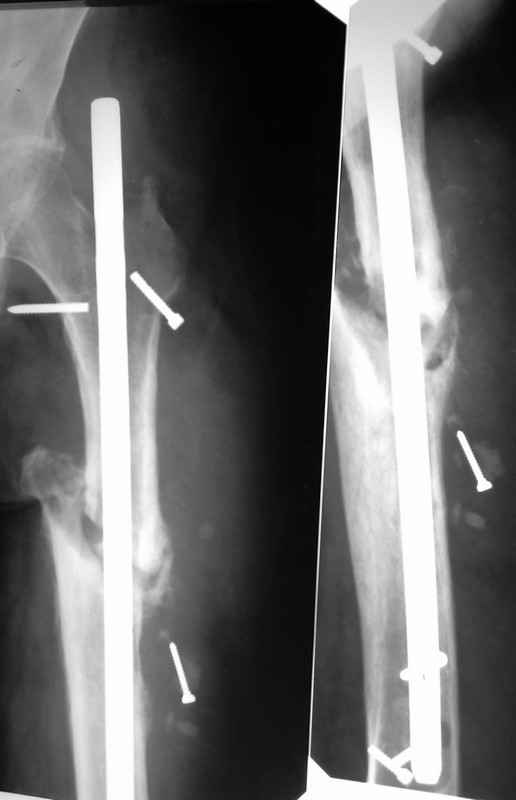

Здравствуйте уважаемые коллеги, прошу Вашего мнения относительно тактики лечения пациента М. 37 лет, рост 170 см. вес 140 кг. Анамнез: пострадал в рез. ДТП в 2004 году, лечился в одной из районных больниц гдебыл прооперирован DCP. в 2006 году перелом м/фиксатора с последующим реостеосинтезом стержнем Кюнчера без блокирования. в 2007 году перелом фиксатора после чего обратился в нашу клинику, где было произведено удаление гвоздя, БИОС L-360 mm D-12 mm с кортико-спонгиозной пластикой, в теч. 6-и мес. больной был под наблюдением динамизация ч-з 2 мес. после чего пациент исчез с поля зрения. Появился с жалобами на болезненность в месте перелома, укорочение ноги, в течении года поочередно в ягодичной области и н/3 бедра функционирующие свищи. На данный момент имеем свищ в н\3 бедра, укорочение ноги на 3 см, внешняя ротация.Произведена фистулография, взят посев из свищевого хода. Планируется: - Удаление м\фиксатора и всех винтов(за исключением проксимального) - I&D с рассверливанием до 16 мм. - кортикотомия, открытое устранение деформаций - БИОС стержнем L-360 mm D-12 mm с а.б. покрытием - бусы с ванкомицином в области свищей

Уважаемый Илья! Если я правильно понял, фистулография у Вас - вторая картинка, а ранки на первой фотографии в области нижних блокирующих винтов и приблизительно на уровне псевдоартроза. Хотелось бы уточнить, есть ли клинические проявления свища на уровне псевдоартроза, отделяемое и т. д. Это существенно влияет на план операции - если перелом неинфицирован,а инфекция только на уровне нижних блокирующих винтов, достаточно удалить конструкции, те, что доступны, не стоит гоняться за кончиками винтов, произвести остеосинтез по Илизарову (на уровне малого вертела стержни, конечно)с п о с т е п е нн о й коррекцией угловой и ротационной деформаций. Параллельно ревизовать место расположения нижнего блокирующего винта, рассверлить, почистить, дренировать.

Если же инфекция и внизу, и на уровне перелома, без тщательной ревизии его не обойтись, не исключено, что потребуется резекция большей или меньшей части диафиза, в последующем или сразу билокальный остеосинтез, что у больного с такими формами далеко не подарок. Или уж идти на укорочение, если резекция будет не очень большой, а после сращения и купирования остеомиелита удлинять, если он еще сам захочет. Успехов. Можете написать на mail, если хотите, вот адрес lobanov.in@gmail.com